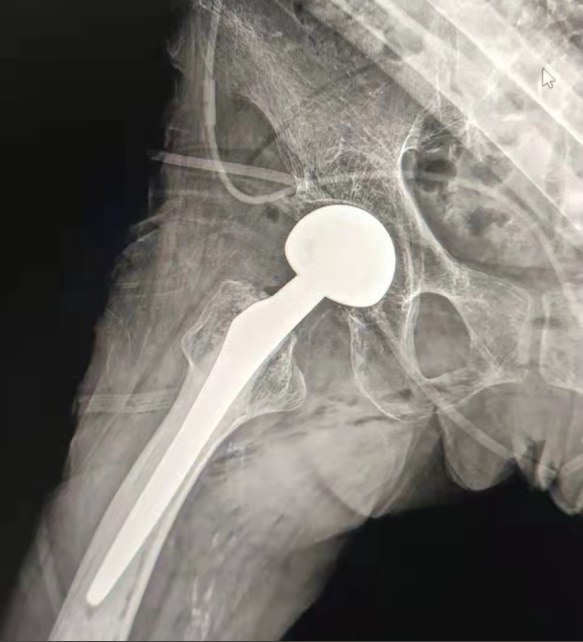

Case Sharing | 70-летний пациент, получивший полную замену тазобедренного сустава цементированной тазобедренной системой Lepu

Цементированная тазобедренная система:

Материалы сплава Ко-Кр-Мо

Высокая износостойкость

Большая механическая прочность

Дизайн плечевой резьбы

Легко установить, удерживать и регулировать угол

Полированная обработка поверхности

Для достижения отличного врастания кости Обеспечение стабильности ранней фиксации

12/14 Стандартный дизайн конуса

Proximal Mix Anatomy

Дизайн Коллекция Европа и США Особенности стебля

Дистальная обработка вырезывания Адге обеих сторон

Снижение давления в медуллярной полости